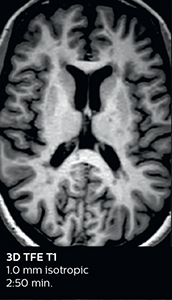

Fast MS protocol with optional sequences

The abbreviated MS protocol for brain is only around 9 minutes, so in case of suspected multiple sclerosis, one or two more advanced sequences may be added, such as PSIR (phase sensitive inversion recovery) or susceptibility-weighted sequences to help us make more confident diagnoses in these inflammatory cases.

3D TFE T1